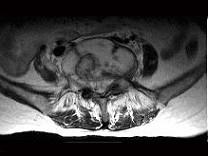

问题 男,35岁,曾有结核病史,现有午后发热,夜间盗汗等,腰部疼痛,活动时加重,休息后减轻,请结合所提供图像,选择最佳答案 ( )

选项 A、腰椎结核 B、多发性骨髓瘤 C、腰椎骨转移 D、腰椎退行性变 E、骨巨细胞瘤

答案 A